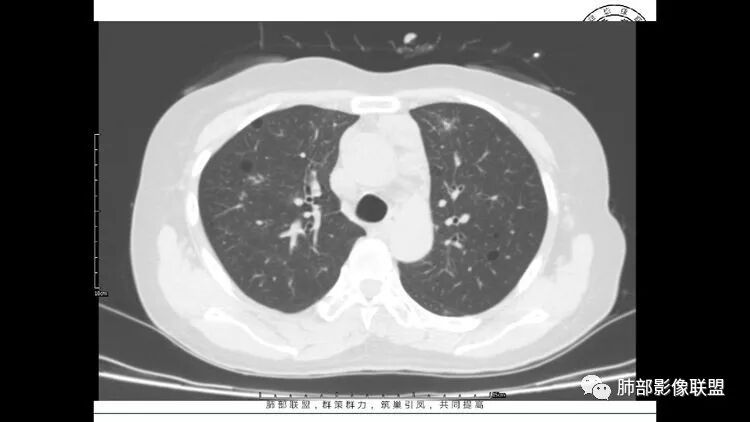

老年女性,眼炎入院,血常规正常,双肺多发囊状影,病变随机分布,形态单一,与血管关系密切,考虑LIP。左下肺混合GGO,边界尚清,贴近囊腔,鉴别腺癌。炎症指标无异常暂不考虑感染性病变。

胸CT:1.双肺多发囊性变,以中下肺为主,病变边缘可见肺动脉,部分囊内可见分隔及肺动脉,双下部分肺野周围可见小叶中心结节及树丫征。

2 左肺上叶尖后段 右肺上叶前段 右肺下叶外基底段 结节影,边界清楚,可见柔软毛刺,左肺下叶后基底段混合密度影。

3.纵隔淋巴结肿大?,以主动脉弓为界向上向下增大。

双肺多发磨玻璃结节,其内可见空腔,周围边界清晰,多发囊,左肺实性结节。考虑间质性肺炎,LIP可能性大。鉴别腺癌。

双肺下叶分布为主的间质改变(磨玻璃影、小叶间隔增厚)、散在气囊影(常有血管贴边)、边界不清小结节